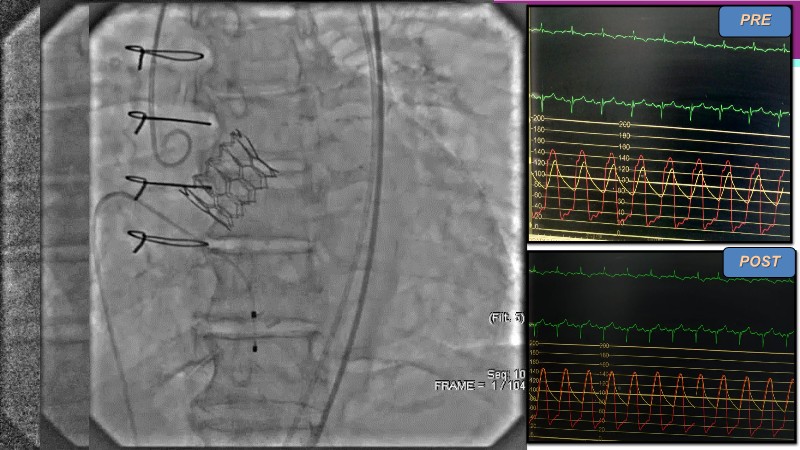

Explore the future of complex PCI with Meril Life’s advanced solutions. Learn about thin-strut platforms, dedicated stents for side branches and diffuse lesions, the role of drug-eluting balloons in metal-free PCI, and the clinical potential of the Myval THV technology.

- To learn about the novel Myval THV technology, its key features, procedural and clinical benefits and learn about the clinical data in a vast cohort of patient population